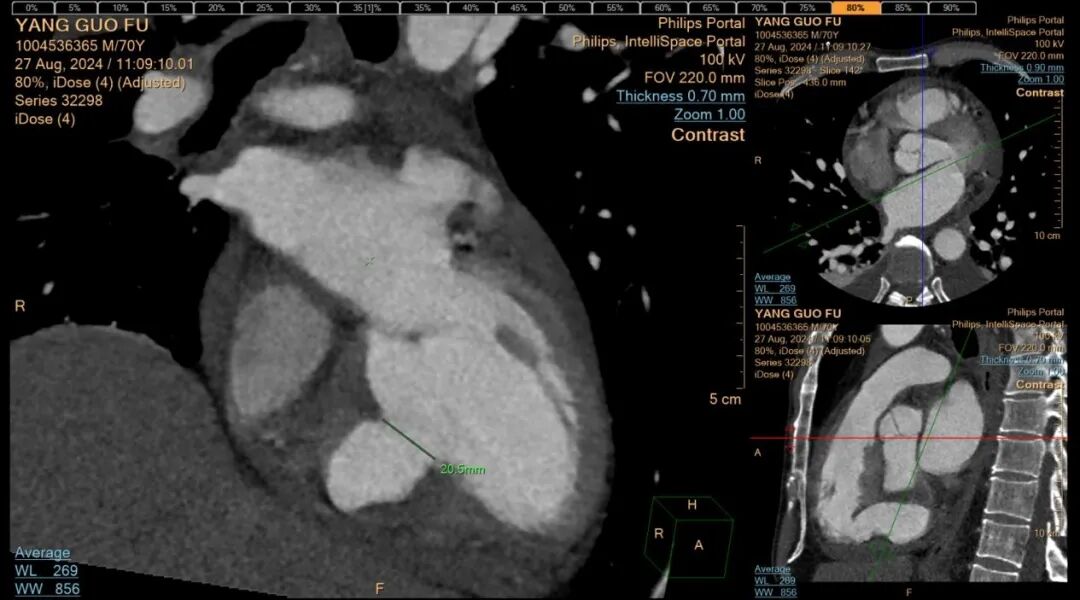

胸痛中心急救电话 17785233019 近年来,贵州航天医院各科室紧跟医学前沿,不断强技术、补短板,大力开展新技术、新项目,完成了许多高精尖、高难度、本地区“首例”的技术,填补了医院医疗技术空白,满足了群众日益增长的医疗需求。 本期,我们将为大家带来心血管内科特色技术——急性心肌梗死伴发室间隔穿孔微创介入封堵术(贵州省内可独立完成此项手术的医院屈指可数)。 案例分享 近期,一名面色苍白、大汗淋漓的患者因急性胸痛被紧急送往我院急诊科,当时患者还伴发严重的急性心衰和心源性休克,病情十分危重,我院急诊科和心血管内科团队当即为患者进行心电图和心脏彩超检查,并在最短时间内得出检查结果,心电图提示:急性下壁ST段抬高型心肌梗塞,心脏彩超提示:急性心肌梗死引发室间隔穿孔。抢救团队争分夺秒,为患者紧急实施了冠脉造影及支架植入治疗,成功稳定了患者的生命体征。 然而,急性心肌梗死引发的室间隔穿孔是一个极为棘手的问题,心血管内科深知开展此例手术的风险性,对此高度重视,立即组织超声科、麻醉科、医学影像科、心脏外科、介入手术室、重症医学科等科室进行多学科讨论(MDT),并在各科室的配合下开展急性心肌梗死伴发室间隔穿孔微创介入封堵术。 考虑患者手术风险大,疼痛刺激可能会加重交感兴奋再次诱发恶性心律失常风险,心血管内科团队在全麻下进行室间隔穿孔封堵治疗,通过穿刺右股静脉、右股动脉,常规行冠脉造影复查冠脉支架通畅,未见狭窄及血栓;又通过DSA进行左心室造影,再次评估室间隔缺损大小,最后成功为患者封堵室间隔穿孔,术后患者病情平稳,住院观察5天后顺利出院。 急性心肌梗死伴发室间隔穿孔这类病例,自然病程8周内的死亡率高达75%,24小时内死亡率也高达25%,此类手术难度系数相当大且死亡率极高。该例患者的及时、成功救治,展现出我院多学科在应对急危重症诊疗工作时所具备的强大实力,更凸显出我院在疑难重症诊治方面的责任与担当。 什么是急性心肌梗死伴发室间隔穿孔 急性心肌梗死后室间隔穿孔(ventricular septal rupture,VSR)是心肌梗死后严重但可以治疗的机械并发症。由于急性心肌梗死后室间隔发生缺血并出现破裂导致的继发性室间隔缺损。 急性心肌梗死伴发室间隔穿孔微创介入封堵术原理 急性心肌梗死伴发室间隔穿孔微创介入封堵术属于外科手术,是利用室间隔穿孔封堵器(哑铃状,左右两边各有一个圆盘,腰呈圆柱体)进行手术,封堵器腰部在释放前收入导管中,导管通过血管到达心房后,放入缺损的位置,在X光机和超声双重定位下,打开封堵器左室盘堵住缺损,再释放右室盘,将室间隔缺损夹在两个圆盘中间,实现对缺损的封堵。 急性心肌梗死伴发室间隔穿孔微创介入封堵术优势 创伤小,痛苦少,疗效迅速,患者普遍易于接受。 贵州航天医院心血管内科 专家团队 姜黔峰 国务院政府特殊 津贴专家 二级教授 博士研究生导师 医学博士 学科带头人 主任医师 贵州省千层次人才,遵义市15851二层次人才。中国胸痛中心执委会委员,国家放射与治疗临床研究中心“国家胸痛中心专家委员会"副主席,中国医疗保健国际交流促进会第二届高血压分会委员,中国医师协会全国高血压专业委员会第一届青年委员,中华老年医学学会心血管分会委员,中国高血压联盟第六届理事会理事,亚太心脏联盟结构性心脏病第一届委员会委员,贵州省中西医结合学会心血管病分会副主委,中华医学会贵州省心脏起搏与电生理分会常委,中华医学会贵州省老年医学分会常委。完成多项省、市级科研课题,主持国家自然科学基金1项。已在国内外期刊发表学术论文100余篇。 临床擅长:高血压、冠心病、心衰的诊治及心血管疾病的介入治疗,尤其擅长先天性心脏病微创介入治疗,已成功完成介入手术治疗2000余例 沈万贵 心血管内科主任 副主任医师 专业擅长:从事临床工作约33年,对冠心病,高血压病,各种心肌病等疾病的诊治以及内科疑难杂症疾病的诊疗具有丰富诊疗经验,累计实施冠心病、外周血管等疾病的介入手术诊疗过万例。擅长于冠脉复杂病变的介入手术治疗、肾动脉狭窄介入手术、下肢深静脉血栓的介入手术治疗。 贵州省医学会心血管病分会常务委员、贵州省心脏病康复医学会常务委员,遵义市医学会心血管病分会副主任委员,西南高血压病管理委员会常务理事,贵州省冠心病组委员;发表学术论文20余篇。 张羽坤 心血管内科 主任医师 专业擅长:具备心血管疾病心律失常介入(导管消融及植入器械)国家级手术资质,参与各类心脏介入手术6000余例。以第一作者在国内核心期刊发表医学论文10余篇,主持市级科研项目1项。 硕士研究生,曾先后前往贵州省人民医院、国家心脏中心北京阜外心血管病医院学习深造(2017年11月至2018年11月参加第二期黔医人才计划并获得优秀学员称号),2022年获得贵州省“第二届最美劳动者”称号。 中国医疗保健国际交流促进会心律与心电分会第三届委员,中国老年医学学会心血管病分会第二届委员会基层委员,贵州省心电生理与起搏分会委员,贵州省中西医结合学会心血管专业委员会委员,遵义医学会心血管病学分会常委,遵义市医学会(第六届)理事会理事,遵义市健康科普专家;是遵义医科大学科技学院及遵义医药高等专科学校兼职教师。 李树刚 心血管内科 副主任医师 专业擅长:具备冠心病介入手术治疗资质,对心内科各种常见病、多发病及急性冠脉综合征疾病具有丰富的临床诊治经验,完成各项冠心病介入治疗6000余台。 毕业于遵义医学院临床医学专业,以第一作者在国内核心期刊发表医学论文数篇,主持并结题市级科研项目1项;遵义市医学会心血管病分会委员,遵义市健康科普专家成员。 胡兴丽 心血管内科 副主任医师 专业擅长:对心血管及内分泌相关常见疾病的诊治及抢救工作具有丰富的临床经验,擅长心血管及心律失常的介入手术。 2009年毕业于遵义医学院临床医学专业,临床工作10余年,有外出进修 CCU 学习经历,发表论文数篇。云贵川高血压联盟委员。 杨 菊 心血管内科 副主任医师 临床擅长:具备心血管疾病冠脉介入手术资质,参与各类冠心病介入手术3000余例。 医学硕士,遵义市医学会心血管病分会委员,多次获得“优秀党员”、“优秀帮扶对象”、“优秀带教老师”等荣誉称号,遵义医药高等专科学校及遵义医科大学科技学院兼职教师;以第一作者在国内核心期刊发表医学论文数篇,主持并结题市级科研项目1项。 张 禹 心血管内科 副主任医师 临床擅长:熟练掌握冠心病、心律失常、高血压、心力衰竭、风湿性心脏病、扩心病等心血管疾病诊治,以及急、危、重症病人的救治。 2017年在重庆第三军医大学新桥医院心内科进修学习,2018年贵州省人民医院进修心律失常介入治疗,取到心血管疾病心律失常介入(导管消融)国家级手术资质,参与冠脉介入、射频消融、起搏器置入等心内科介入手术4000余例;是遵义市医学会心血管病分会委员。 李茂春 心血管内科 副主任医师 临床擅长:1995年毕业于遵义医学院临床医学系,从事临床工作28年,熟练掌握高血压、冠心病等心血管疾病的诊治及危急重症患者的救治,擅长糖尿病、甲状腺功能亢进、代谢综合征等内分泌代谢性疾病的诊治,在多年的临床工作中对内分泌代谢疾病、心血管疾病的诊治中积累了丰富临床的经验。 贵州省医学会内分泌暨糖尿病学分会第七届委员会甲状腺学组组员,遵义市内分泌暨糖尿病学分会第一届委员会常务委员,贵州省康复医学会骨内科专业委员会遵义地区分会常务委员。多年来在省内外期刊发表论文数十篇。 刘忠凤 心血管内科 副主任医师 临床擅长:对结构性心脏病超声心动图的判读及解析、结构性心脏病的诊疗有丰富的临床诊疗经验;擅长心血管常见多发病及难治性心衰的诊治、恶性心律失常的抢救。 遵义市医学会心血管病分会委员,遵义市医学会内分泌暨糖尿病分会委员,遵义市医学会骨质疏松暨骨矿盐疾病学分会委员;曾前往贵州省人民医院超声心动图室、四川大学华西医院超声科进修学习超声图;发表省级期刊数篇,参与结构性心脏病术中超声指导。 贵州航天医院心血管内科简介 • ✦ 基本情况 ✦ • 贵州航天医院心血管内科编制床位60张,配置了29台24小时动态心电图、110台24小时动态血压、心脏除颤仪、监护仪、输液泵、微量注射液,同步12导联、18导联心电图机、临时心脏起搏器、床旁血糖仪、主动脉内球囊反搏、食道超声、血管内超声诊断仪及DSA心血管诊疗等。 • ✦ 学科、专科建设 ✦ • 近年来成功获批胸痛中心、房颤中心、儿童先天性心脏病定点救治单位授牌;是遵义市临床重点专科、远程心电示范中心、高血压慢病管理示范中心。 • ✦ 诊疗范围 ✦ • 开展了急诊冠脉介入诊疗,冠脉复杂病变介入术、冠状动脉斑块旋磨术、心脏再同步治疗起搏器植入术、心脏再同步治疗除颤器植入术、射频消融术【心房颤动(导管消融、冷冻消融)、心房扑动、房性心动过速、室性心动过速、室性早搏】、结构性心脏病介入治疗【房间隔缺损(卵圆孔未闭)封堵术、室间隔缺损封堵术、动脉导管未闭封堵术、冠状动脉瘘封堵术、左心耳封堵术等】、临时起搏器植入术、常规永久起搏器植入术(双腔、单腔)、下肢动静脉造影术、下腔静脉滤器植入及取出术、自主肾上腺静脉采血、颈动脉支架植入术、外周动脉支架植入术、肾动脉支架植入术等,积极开展冠脉内超声检查、FFR、OCT、心脏射频三维手术、房颤一站式治疗(房颤射频消融术+左心耳封堵术)、主动脉瓣介入术等,并邀请院外专家指导成功开展腹主动脉支架植入术。 • ✦ 咨询信息 ✦ • 门 诊 地 址:贵州航天医院呼吸综合楼1楼013诊室。 住院病区 地 址:贵州航天医院外科综合楼9楼 咨询电话 护士站:28611793 医生办公室:27677832